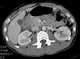

Trauma with duodenal perforation

Gastrointestinal perforation, also known as ruptured bowel, is a hole in the wall of part of the gastrointestinal tract. The gastrointestinal tract includes the esophagus, stomach, small intestine, and large intestine. [Source: Wikipedia ]